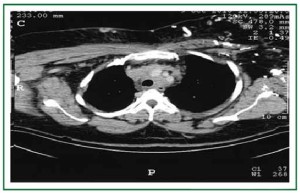

A trial of itraconazole has been initiated and a superior vena cava stent has been placed via trans-jugular access (Figure 2). The patient’s severe edema and symptoms started to recede within a day of the interventional procedure.

Figure 2. Trans-jugular passage of Kumpe catheter into the Superior Vena cava -- balloon angioplasty and placement of Viabahn covered stent.